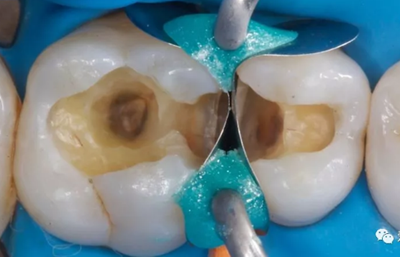

八、繼發(fā)齲

(一)原因

腐質(zhì)未去凈。充填體邊緣不密合:原因包括修復(fù)體飛邊折斷;樹脂材料自身聚合收縮;夾在充填體和洞側(cè)壁或齦壁的充填材料溶解。

如 PPT22 圖示下為臨床治療常見的邊緣白線,造成了充填體邊緣的不密合,圖上是治療的時腐質(zhì)沒有去除干凈,繼續(xù)發(fā)展以后出現(xiàn)摸尋狀的改變。